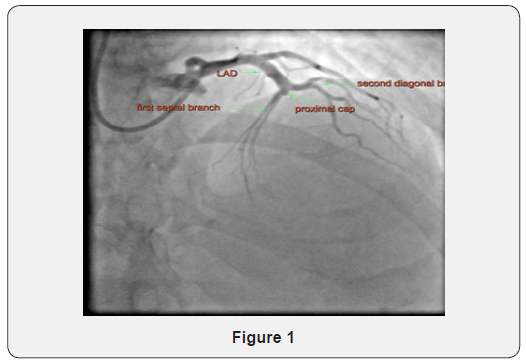

His index event had likely occurred 4 months previously in Gambia, for which he had not sought medical attention. He had presented to his GP, now asymptomatic and had been found to have an abnormal ECG with persisting anterior ST elevation and deep T wave inversion. He had an echocardiogram which demonstrated a left ventricular ejection fraction of 40% with a hypokinetic anterior wall and apex with preserved LV wall thickness in the LAD territories but a likely apical LV thrombus. His bloods demonstrated a normal haemoglobin, an estimated glomerular filtration rate of 52 ml/min. 1.7 m2 and normal troponins. He underwent coronary angiography via a distal right radial artery approach using a 6 French Terumo Glide-sheath Slender. A 5.2 French (F) diagnostic Super Torque Plus JR4 catheter (Cordis) and 6 F 3.5 MACH 1 Guide Catheter CLS Curve (Boston Scientific, MA) were used for the diagnostic images. These demonstrated single vessel coronary artery disease (CAD) with CTO with a ambiguous proximal cap in the mid LAD which started at a trifurcation point involving the second diagonal and septal branches (Figure 1).